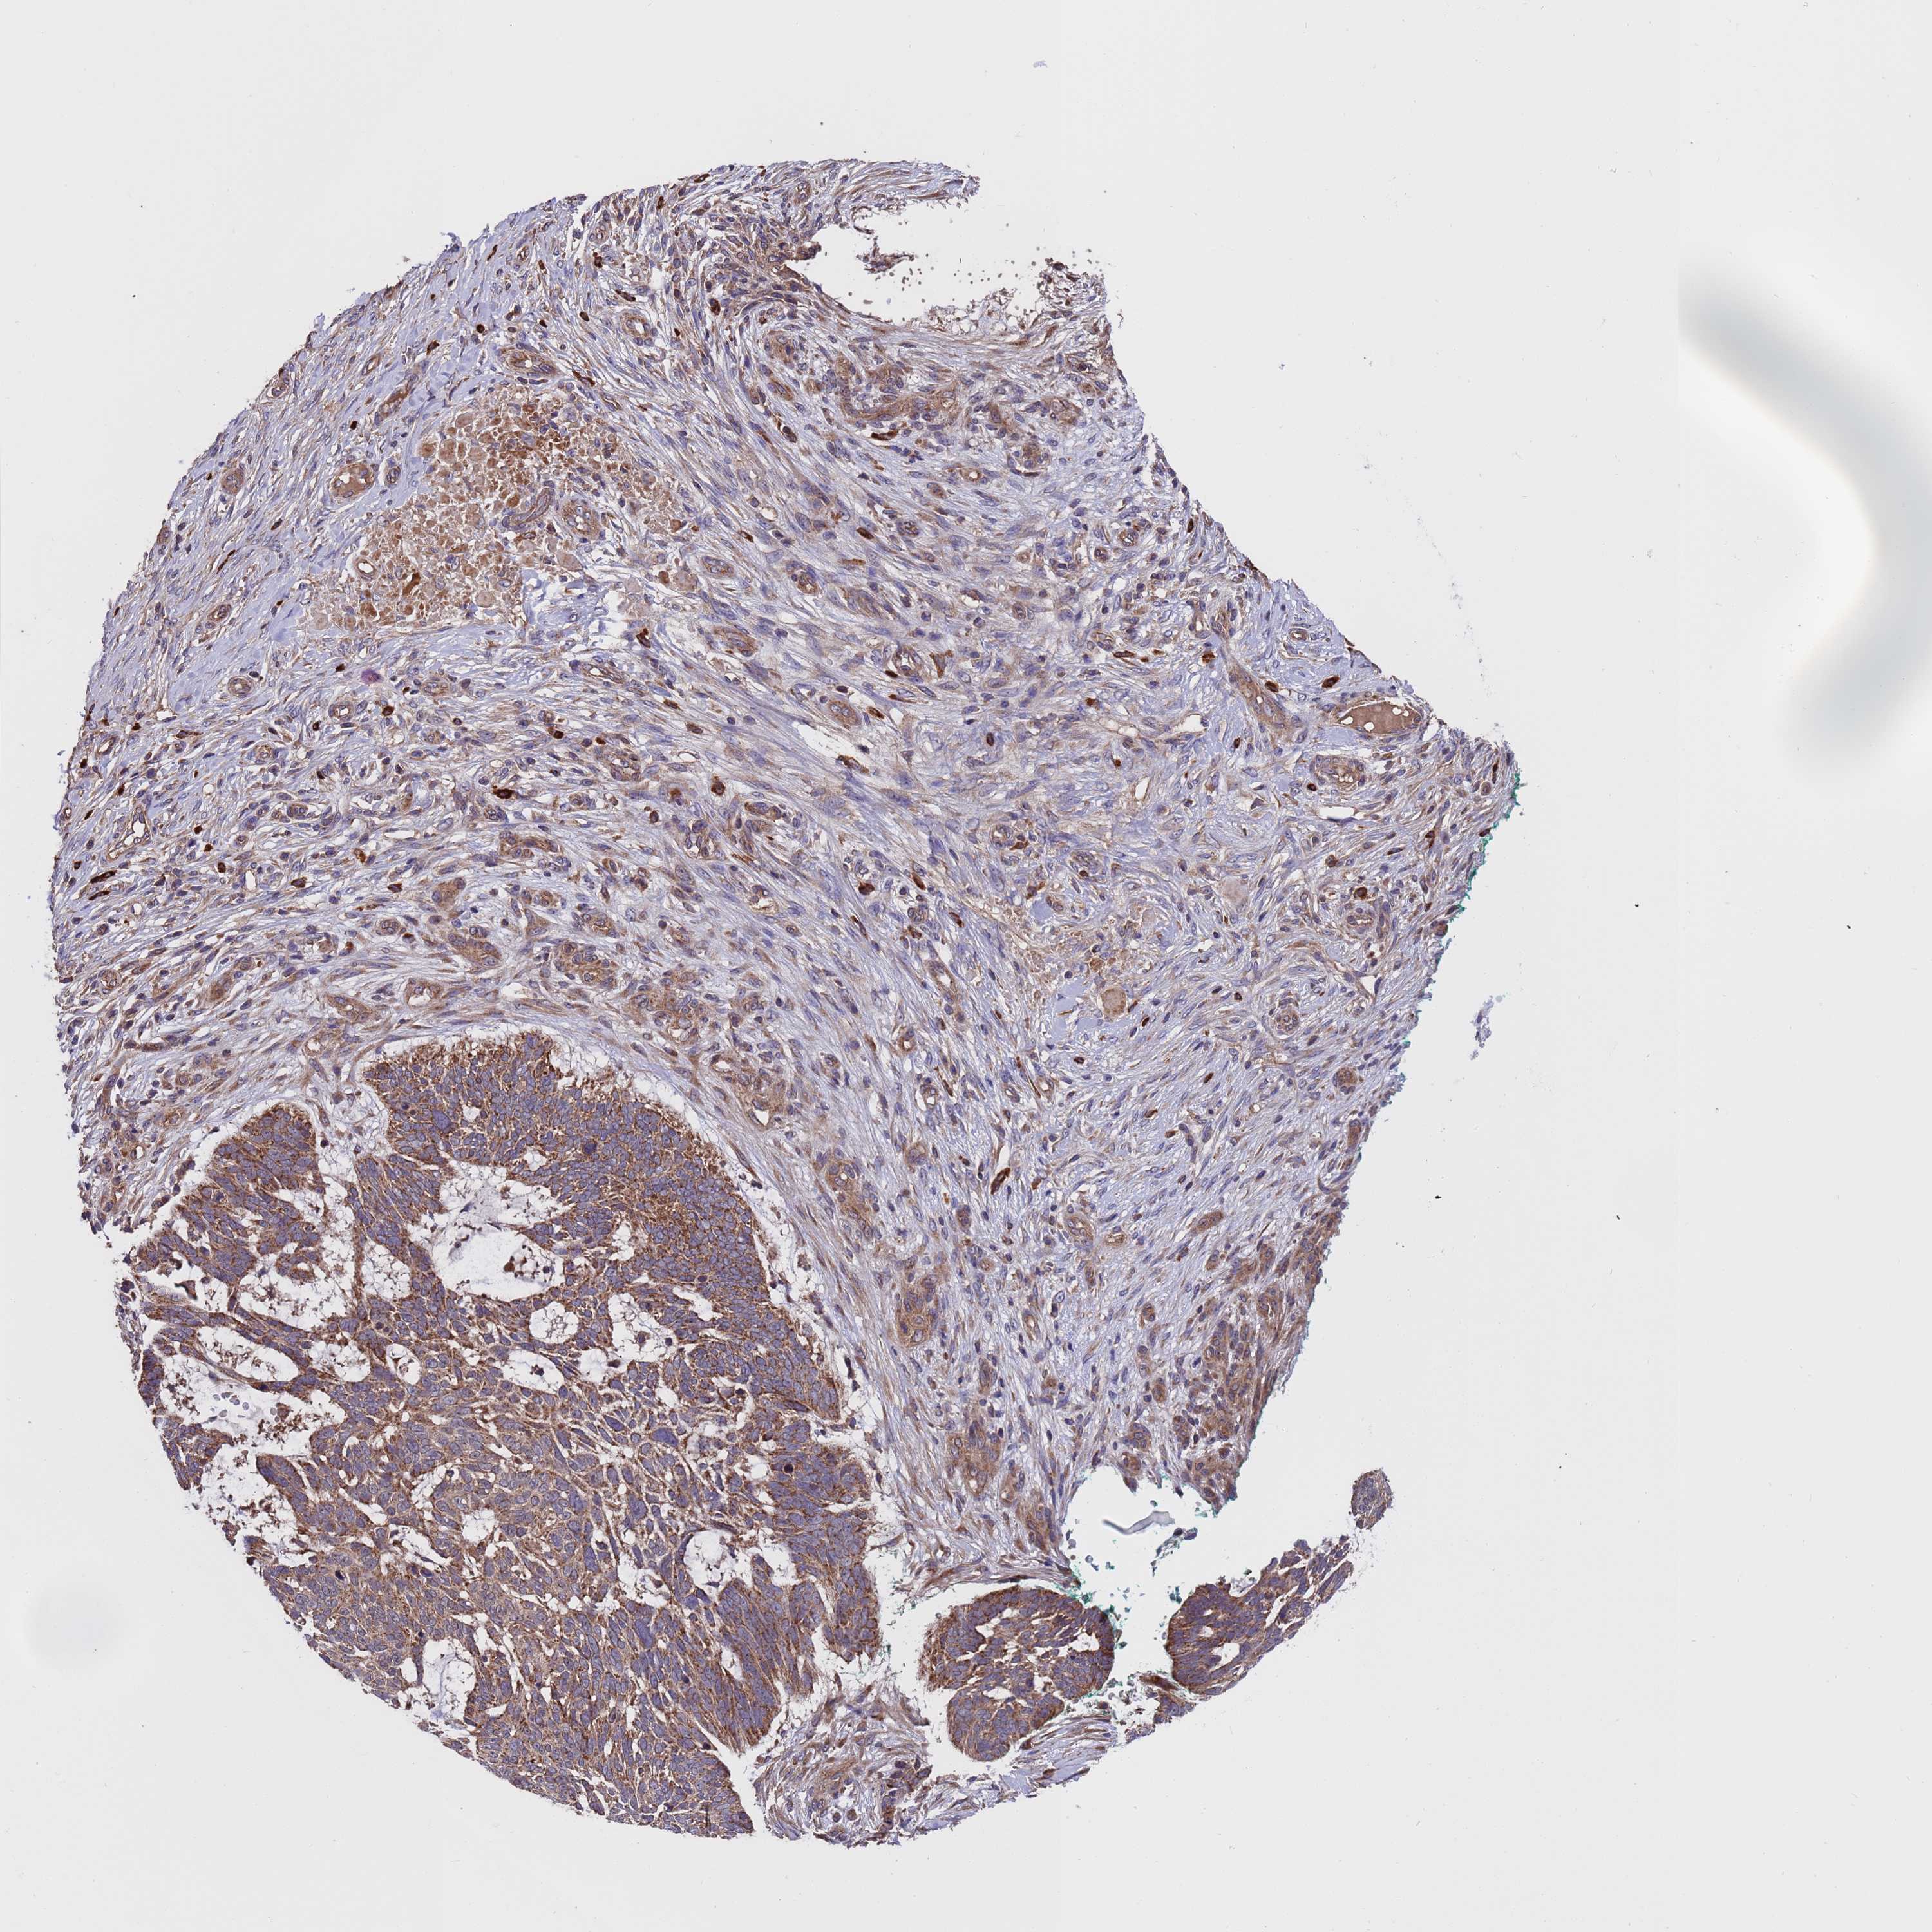

SKIN CANCER - Protein expressioni

A mouse-over function shows sample information and annotation data. Click on an image to view it in a full screen mode. Samples can be filtered based on level of antibody staining by selecting one or several of the following categories: high, medium, low and not detected. The assay and annotation is described here.

Antibody stainingi

Antibody staining in the annotated cell types in the current human tissue is reported as not detected, low, medium, or high, based on conventional immunohistochemistry profiling in selected tissues. This score is based on the combination of the staining intensity and fraction of stained cells.

Each image is clickable and will lead to virtual microscopy that enables deeper exploration of all samples and also displays staining intensity scores, fraction scores and subcellular localization as well as patient and tissue information for each sample.

Antibody HPA046265

Staining

High

Medium

Low

Not detected

Intensity

Strong

Moderate

Weak

Negative

Quantity

>75%

75%-25%

<25%

None

Location

Nuclear

Cytoplasmic/membranous

Cytoplasmic/membranous,nuclear

Squamous cell carcinoma, metastatic, NOS